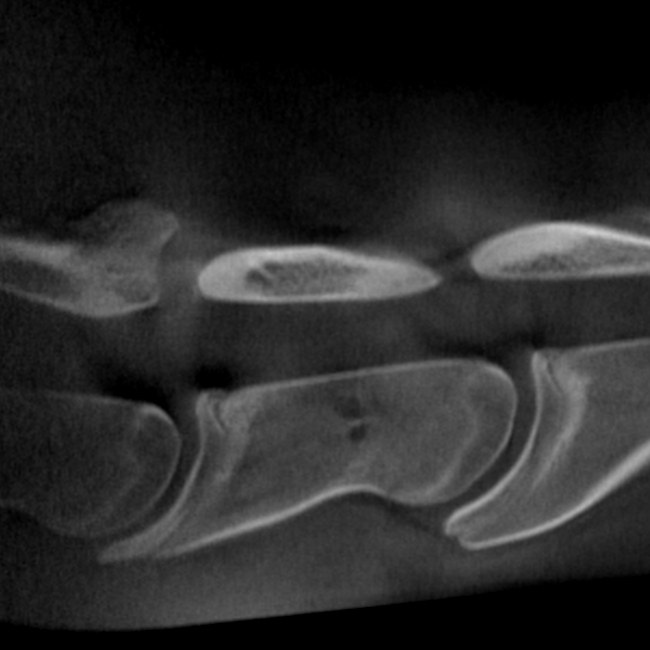

Our High Definition Volumetric Imaging (HDVI) technology represents the most advanced stage of Flat Panel CT technology. It offers exceptional diagnostic imaging for both hard and soft tissues, in diagnostic settings and intraoperative theaters. It is the gold standard for orthopedic applications.

Pegaso enhances safety and usability by enabling the scanning of a standing horse’s head, neck, and limbs.

Scan of the standing horse

Pegaso scans head, neck and limbs of the standing horse